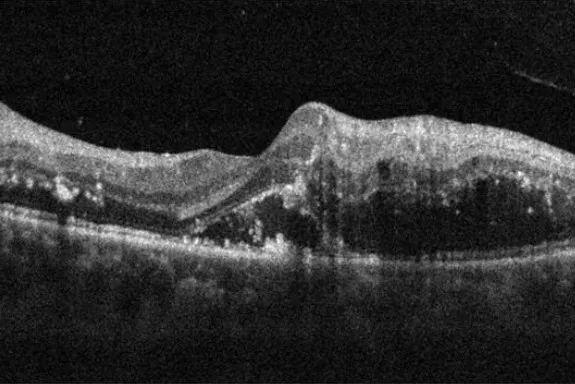

我们可以先看下面的三张OCT图像:

图像均显示黄斑区囊样水肿,而这只是一种体征,而不是某种疾病所特有的,可能多种疾病都会有类似的表现。所以我们还要结合眼底照相来辅助诊断,通过眼底照相我们可以进一步明确疾病。